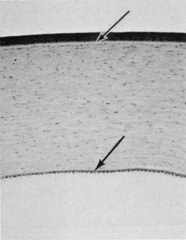

The corneal epithelium is the anterior-most cell layer of the cornea (Fig. 1). It is typically several cell layers thick, consisting of the apical cell squamous layer, the multilayered, polygonal-shaped wing cells beneath the apical layer, and the posterior-most layer of basal cells (Fig. 2). The wing cell layer is two or three cells thick in the central cornea, but tends to be four to five cells thick in the periphery. In total, the epithelium is approximately 50 μm thick in the central human cornea.

Fig. 1. Full-thickness view of the normal human cornea. From top: epithelium, Bowman's layer (arrow), stroma, Descemet's membrane (arrow), and endothelium (hematoxylin-eosin stain, 80×). (Courtesy of Drs. Rodrigues, Waring, Hackett, and Donohoo.)